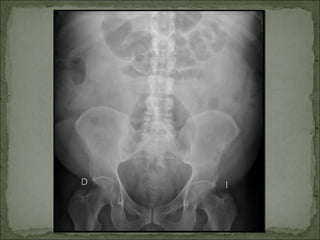

Similar    a Pielonefritis, Rx abdomen: método

evolución tórpida:           inespecífico.

pronóstico.               TC: método de elección.

DIAGNÓSTICO Similar a Pielonefritis, Rx abdomen: método evolución tórpida: inespecífico.  Tipo 1: Mortalidad 70 a Ecografía renal: gas en el 90%. parénquima renal y vías  Tipo 2: Mejor urinarias. pronóstico. TC: método de elección.